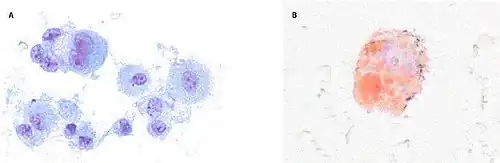

| CT scan of the chest showing diffuse lung infiltrates found in three cases of vaping-associated pulmonary injury | |

There are non-specific laboratory abnormalities that have been reported in association with the disease, including elevations in white blood cell count (with neutrophilic predominance and absence of eosinophilia), transaminases, procalcitonin, and inflammatory markers.[4][66] Infectious disease testing, including blood and sputum cultures and tests for influenza, Mycoplasma, and Legionella were all found to be negative in the majority of reported cases.[66] Imaging abnormalities are typically bilateral and are usually described as "pulmonary infiltrates or opacities" on chest X-ray and "ground-glass opacities" on chest CT.[4]

Bronchoalveolar lavage specimens may exhibit an increased level of neutrophils in combination with lymphocytes and vacuole-laden macrophages.[22] Lavage cytology with oil red O staining demonstrated extensive lipid-laden alveolar macrophages.[66][67] In the few cases in which lung biopsies were performed, the results were consistent with acute lung injury and included a broad range of features, such as acute fibrinous pneumonitis, diffuse alveolar damage, lipid-laden macrophages, and organizing pneumonia.[41][62] Lung biopsies often showed neutrophil predominance as well, with rare eosinophils.[64]